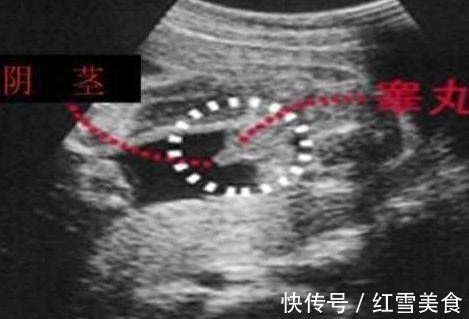

男宝宝的B超图:男宝宝的B超图上其实是能看到小鸡鸡的,图片的红圈处就是,这张图片上的小鸡鸡比较清晰,医生取的那个角度就是宝宝屁股正下方,看的很清楚。凸出的东西 是他的标记: 看到圆圆的是睾丸,如果看到圆圆的如小肠的东西就是全部鸡鸡。